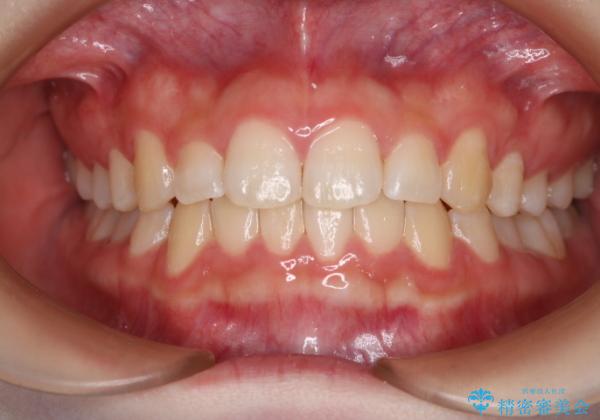

- 前歯のガタつきの改善を主訴に来院された患者様です。

ガタつきによる上顎正中の空隙や歯の突出感も気にされていました。

費用を抑えたいとの事だったので歯の移動量なども考慮し、インビザライン・ライトパッケージでの治療を計画しました。